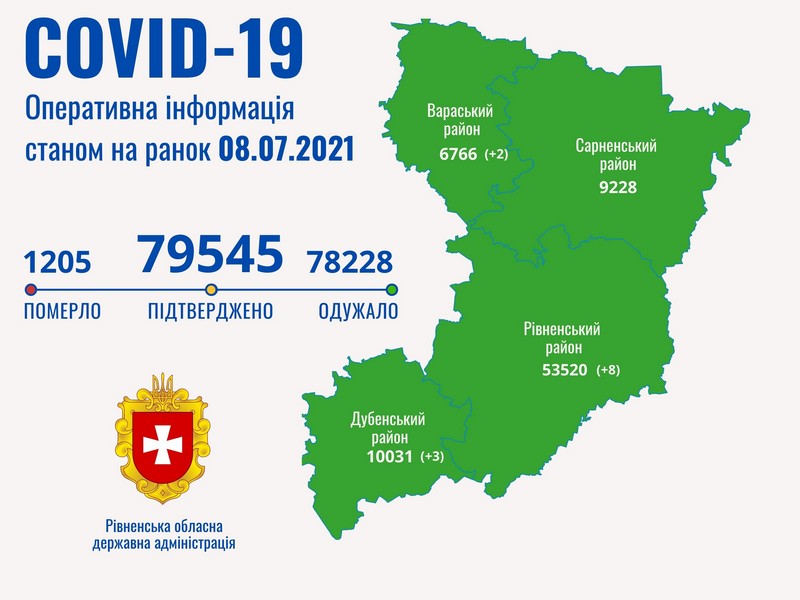

Пів тисячі - у важкому стані, 9 жителів Рівненщини померли за добу від коронавірусу